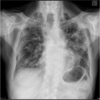

What does this CXR show?

* Right mainstem intubation